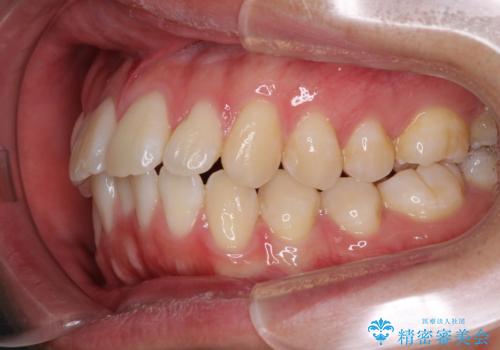

- 全体的なデコボコと、前歯の前に出ている感じを気にして来院された患者様です。

患者様と相談の上、非抜歯にてインビザラインを用いて矯正治療を行うこととし、IPR(歯と歯の間)並びに歯列全体の後方移動により口元の突出感の改善することとしました。

お仕事が忙しい方で、装着時間が不足したり、定期的な通院ができなかったりと、自己管理が重要なインビザラインによる矯正治療が長期化する要因が重なり、5年ほどの期間を要しました。